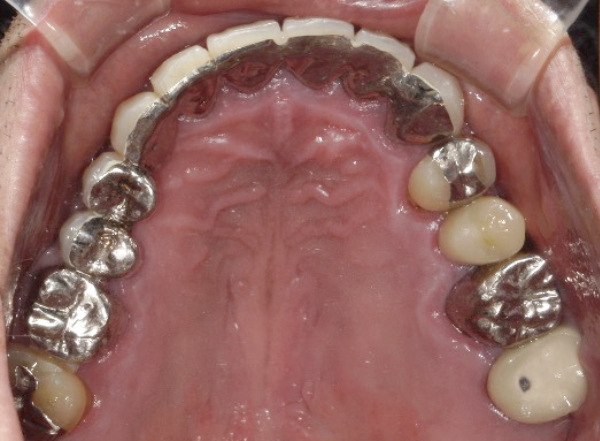

CASE1

セラミックを用いた虫歯治療

| 主訴 | 虫歯の治療と全体的な見た目の改善 |

|---|---|

| 治療期間 | 2ヶ月 |

| 治療費 | セラミック1本 88,000円〜165,000円(税込) デンタルローンで月3,000円から始められます |

| 治療の リスク | 治療には神経の治療や抜歯が必要な場合があります。 虫歯や歯周病を防ぐ為に、定期検診にご来院いただきます。 |